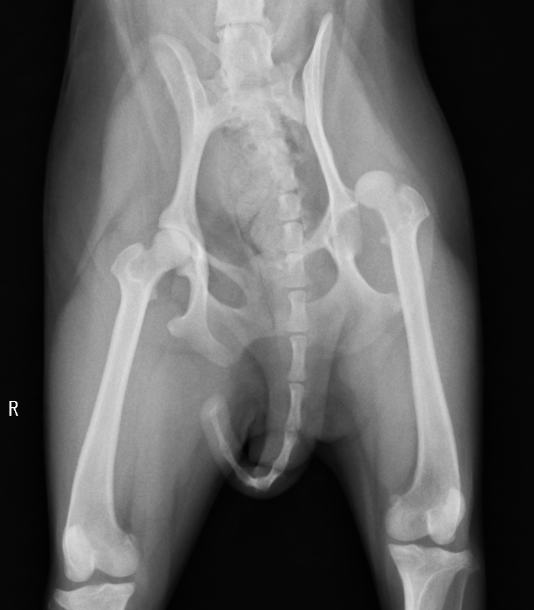

同じ症例ではありませんが、骨頭を切除した症例をご紹介します。症例は8ヶ月のトイプードルで、最近足をあげるということで来院されました。触診では足を伸ばすときに痛がり、レントゲンで骨頭の骨折が認められました。おそらく生まれつきレッグペルテスという病気があり骨頭が折れてしまったのではないかと予想されます。レッグペルテス(=大腿骨頭壊死症)とは主に小型犬種において発生する大腿骨頭の非炎症性無菌性壊死です。犬では生後数ヶ月から1年までに痛みや跛行を主訴に来院されます。原因は大腿骨に栄養が行く血管がうまく発達せず、骨頭の一部が壊死ししてしまうと考えられています。遺伝性と考えられていますが、まだはっきりとしたことはわかっていません。猫でも似たような病態があると最近言われ始めています。

骨頭の一部が折れて潰れてしまっています。